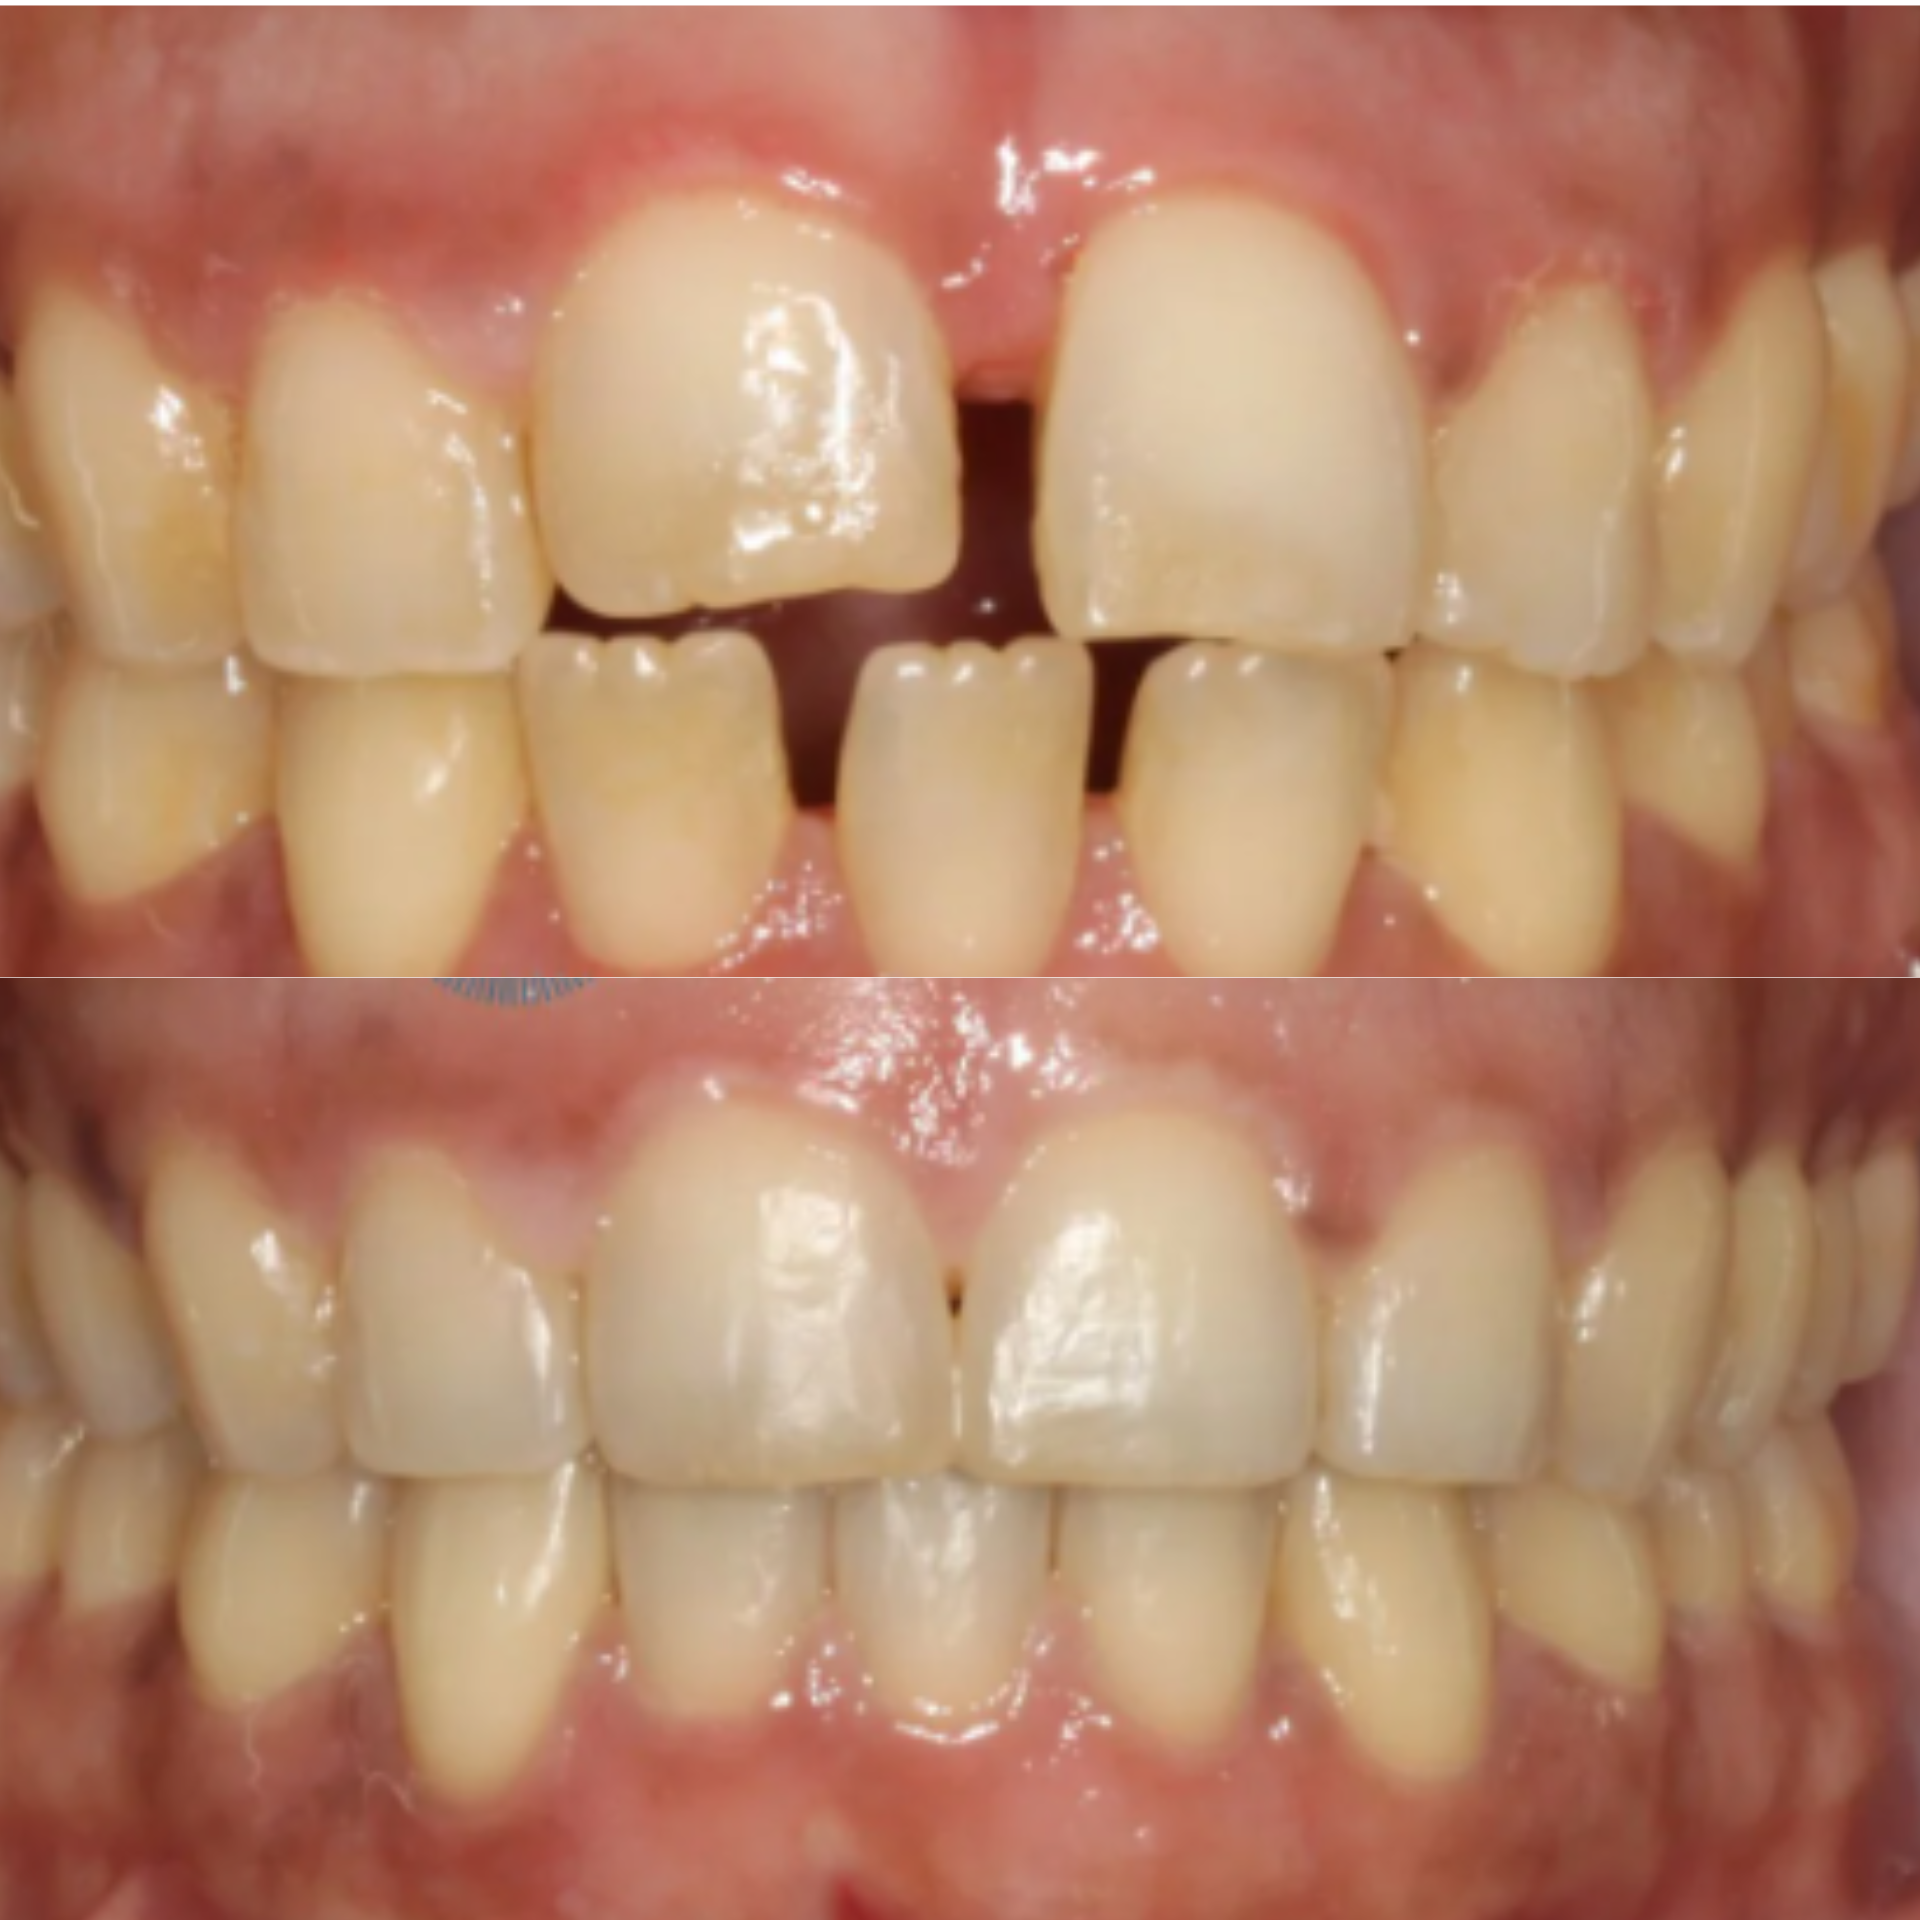

At Elite Dental Group, we provided emergency care that included root canal treatment on the upper central incisors. Dr. Satish Palayam performed an immediate implant placement for the right lateral incisor and completed a crown lengthening procedure on the palatal side of the right central incisor to support proper restoration. A provisional bridge was then placed to maintain both function and esthetics throughout the healing phase.

After a four month healing period, the final crowns were placed on the central incisors, and the implant for the right lateral incisor was successfully restored and finalized.